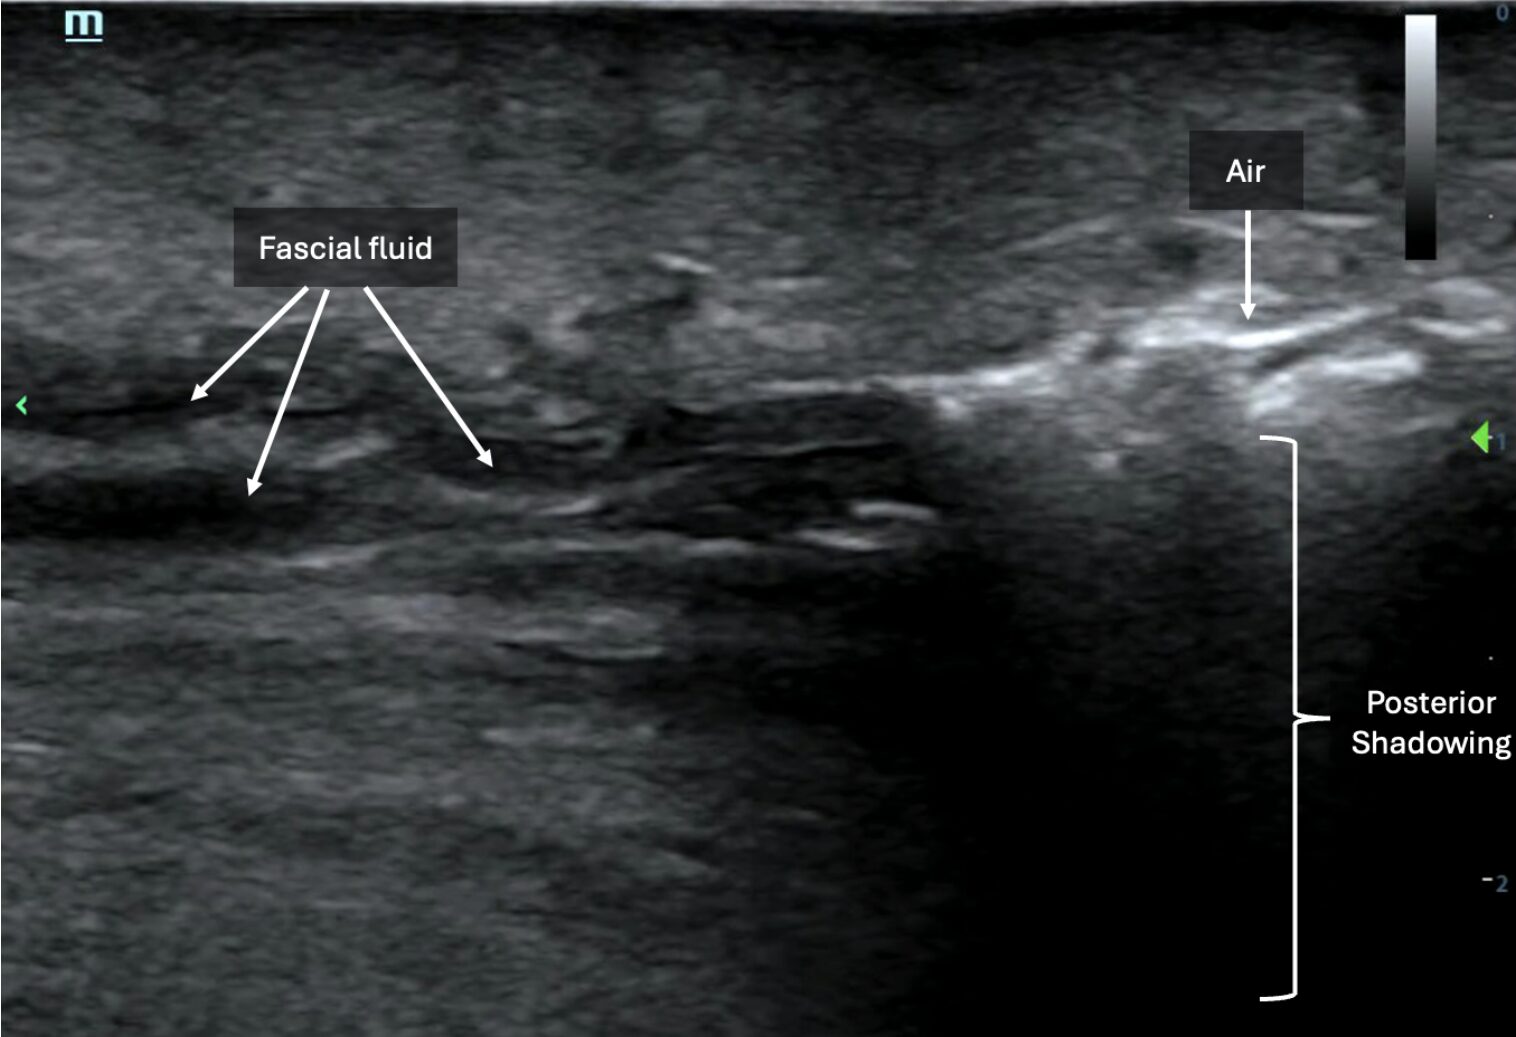

Below is another example of anechoic layering of fascial fluid (left side of image) tracking deep to subcutaneous tissues juxtaposed next to hyperechoic foci of air with posterior shadowing, indicating subcutaneous emphysema (right side of image) (Image 5, Video 4).

Image 5: Image demonstrating presence of subcutaneous emphysema (right side of image) and layering of fascial fluid (left side of image). Images courtesy of Dr. Shepherd and Dr. Alerhand

Video 4 : Video clip of the above still image demonstrating subcutaneous emphysema and layering of fascial fluid. Images courtesy of Dr. Shepherd and Dr. Alerhand